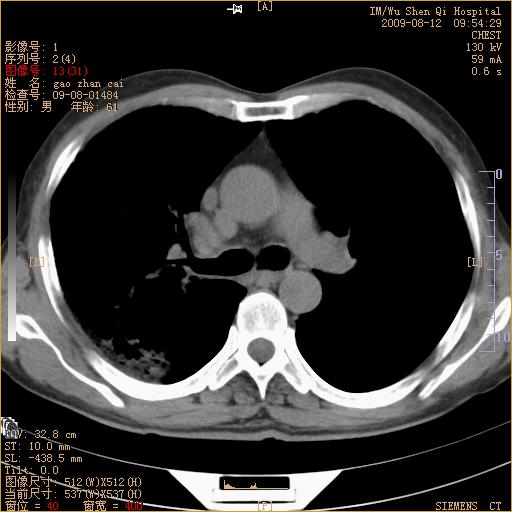

标题: CT21567:咳嗽,咳痰,发热半月余 [打印本页]

标题: CT21567:咳嗽,咳痰,发热半月余

考虑右肺支扩并感染可能,结核不除外,结核生化检查看看。

右肺门区占位待排(图片没有传完)

右肺上叶支扩并感染,肺间质纤维化,肺气肿,右肺门淋巴结肿大。建议抗炎治疗后复查。